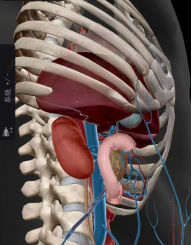

图5 马潞林教授行“腹腔镜下隔离胶植入术”示意图